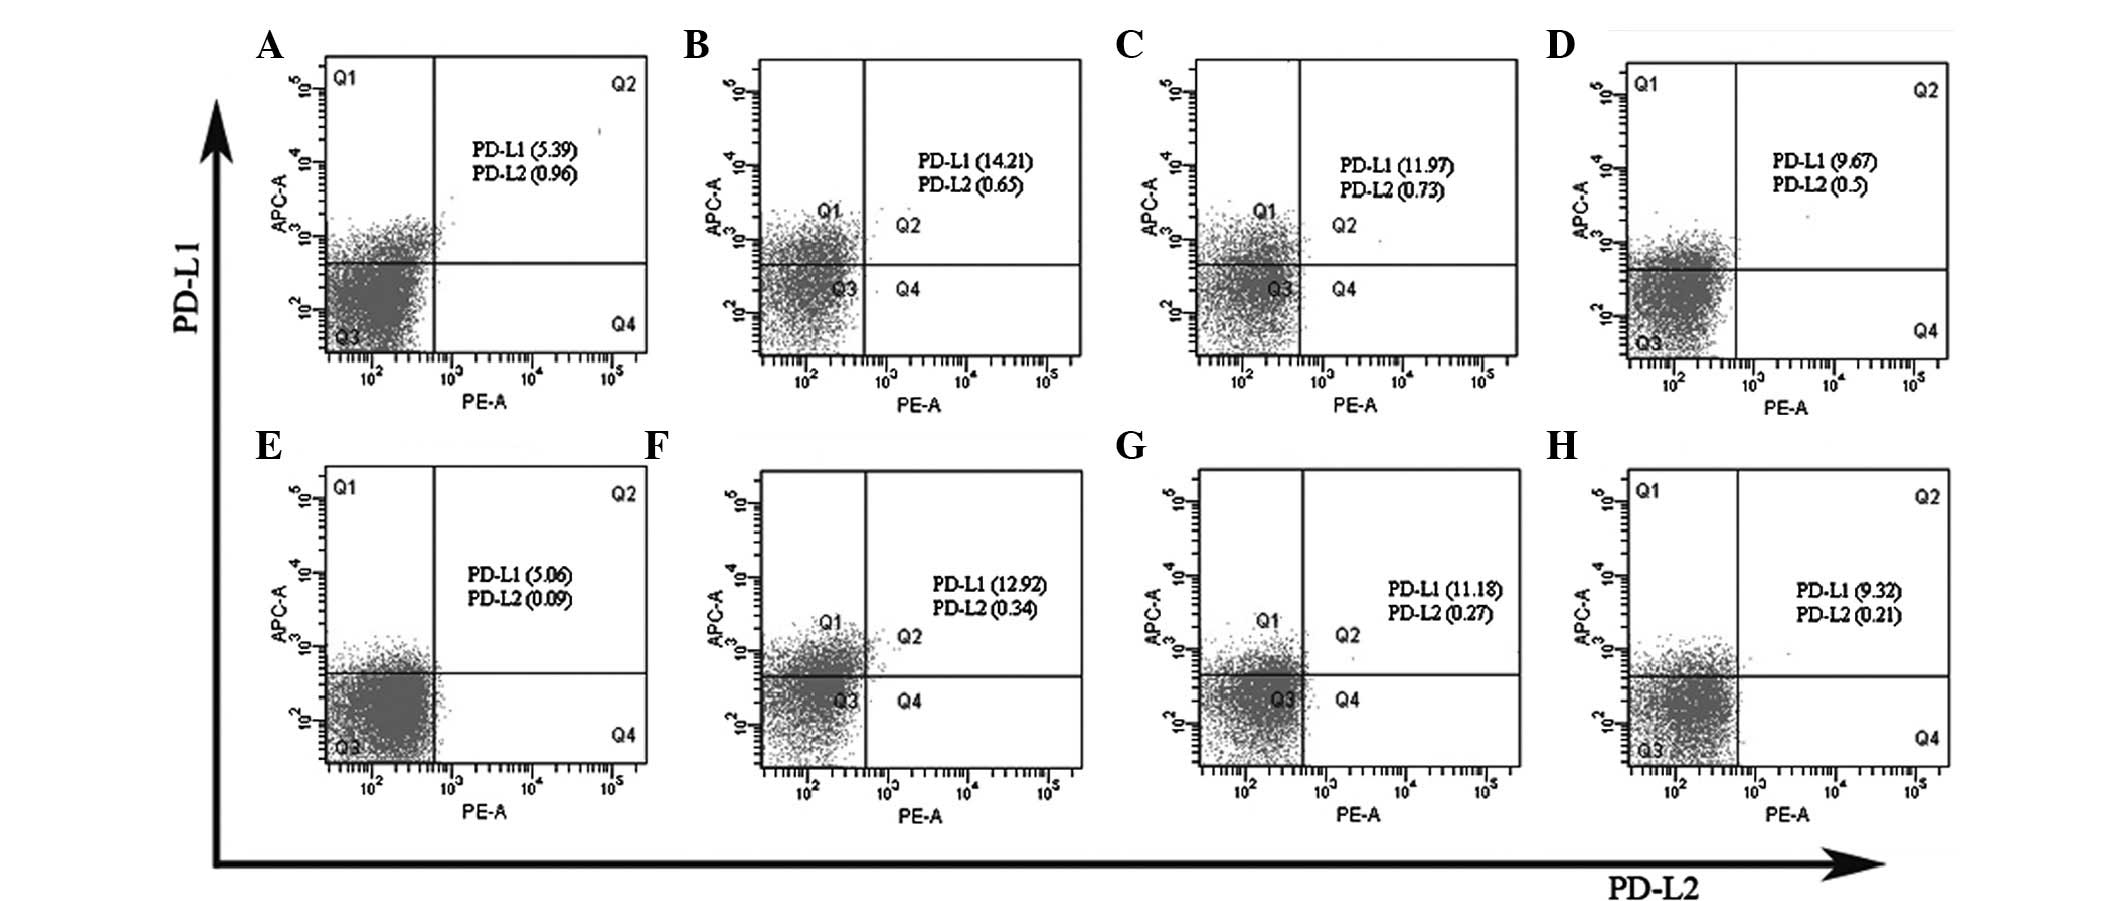

The expression of the PD-L1 and PD-L2 molecules on

the CD4+ and CD8+ T cells in the PBMCs was

investigated by using flow cytometry analysis. As shown in Fig. 3, the constitutive expression of

PD-L1 was detected on the CD4+ and CD8+ T

cells in the PBMCs from the MsPGN patients and the healthy donors.

However, the expression of PD-L2 was hardly detected on the

CD4+ and CD8+ T cells in the PBMCs from the

two groups. The patients with MsPGN were observed to have an

increased PD-L1 expression on the CD4+ and

CD8+ T cells in the PBMCs compared with the healthy

donors. Overall, treatment with sinomenine significantly inhibited

the high expression of PD-L1 on the CD4+ and

CD8+ T cells in the PBMCs from the MsPGN patients,

whereas it had no effect on the expression of PD-L2.